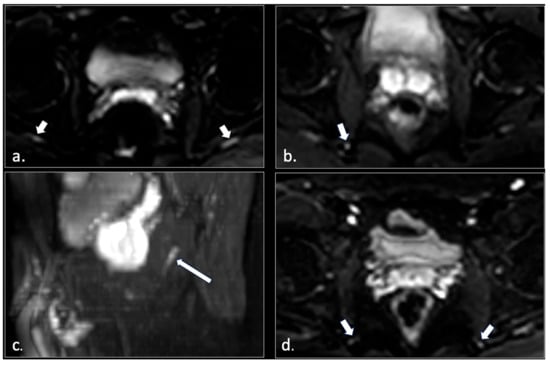

MRI in Chronic Pudendal Neuralgia: Diagnostic Criteria and Associated Pathologies

by Michele Gaeta, Sofia Turturici, Karol Galletta, Carmelo Geremia, Attilio Tuscano, Aurelio Gaeta, Marco Cavallaro, Salvatore Silipigni and Francesca Granata

Diagnostics 2026, 16(2), 326; https://doi.org/10.3390/diagnostics16020326 (registering DOI) - 20 Jan 2026

Background/Objectives: Chronic pudendal neuralgia is a relatively rare condition in the general population, with an incidence of 1%. Although diagnosis of pudendal neuralgia is mainly clinical, Magnetic Resonance Imaging (MRI) is commonly performed to obtain further information. However, clear criteria and guidelines for MRI diagnosis and the clinical–radiological correlation are still not definite. Methods: We reviewed 81 patients with chronic pudendal neuralgia, studied by an MRI designed protocol for a pelvis and pelvic floor examination. A key element of the protocol was the use of a diffusion-weighted imaging (DWI) technique with echo planar imaging (EPI) sequence (b-values of 0, 100, and 600) for the neurographic evaluation of the nerve. Results: MRI examination revealed DWI abnormalities in 42/81 patients. Pudendal nerve abnormalities were unilateral in 33/42 patients and bilateral in 9/42. Moreover, in 23/42 patients, pathologies related to a high probability of neuropathy have been identified. Conclusions: This study highlights the role of pelvic MRI as a valuable imaging modality in the evaluation of patients with chronic pudendal neuralgia. In the study protocol we propose, an essential role is played by the DWI technique, which improves the visual definition of the pudendal nerve and related anatomical structures. By focusing on anatomical visualization and structured image interpretation, our work provides a practical imaging-oriented contribution to a field in which standardized MRI evaluation is still lacking. Full article